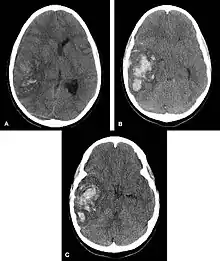

![]() | |

| Multiple intraparenchymal hemorrhage | |

Intraparenchymal hemorrhage (IPH) is one form of intracerebral bleeding in which there is bleeding within brain parenchyma. The other form is intraventricular hemorrhage (IVH).[1]

Computed tomography (CT scan): A CT scan may be normal if it is done soon after the onset of symptoms. A CT scan is the best test to look for bleeding in or around your brain. In some hospitals, a perfusion CT scan may be done to see where the blood is flowing and not flowing in your brain.